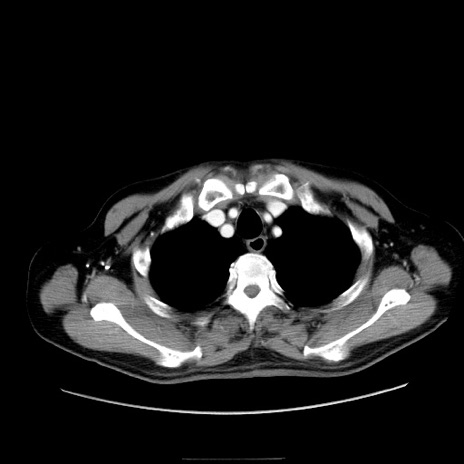

症例30(横断像)

【症例】80歳代男性

【主訴】臍周囲痛

【現病歴】約6時間前から臍下部痛が出現。次第に腹部膨隆・背部痛も生じてきたため来院。背部痛の場所は変化しない。

【身体所見】意識清明、BT 36.3℃、BP  131/87mmHg、P 87bpm、SpO2 100%(RA)、臍周囲自発痛・圧痛あり、反跳痛なし、自発痛部位に一致して板状硬あり、腹部膨隆、腸雑音減弱、CVA tenderness両側陰性。